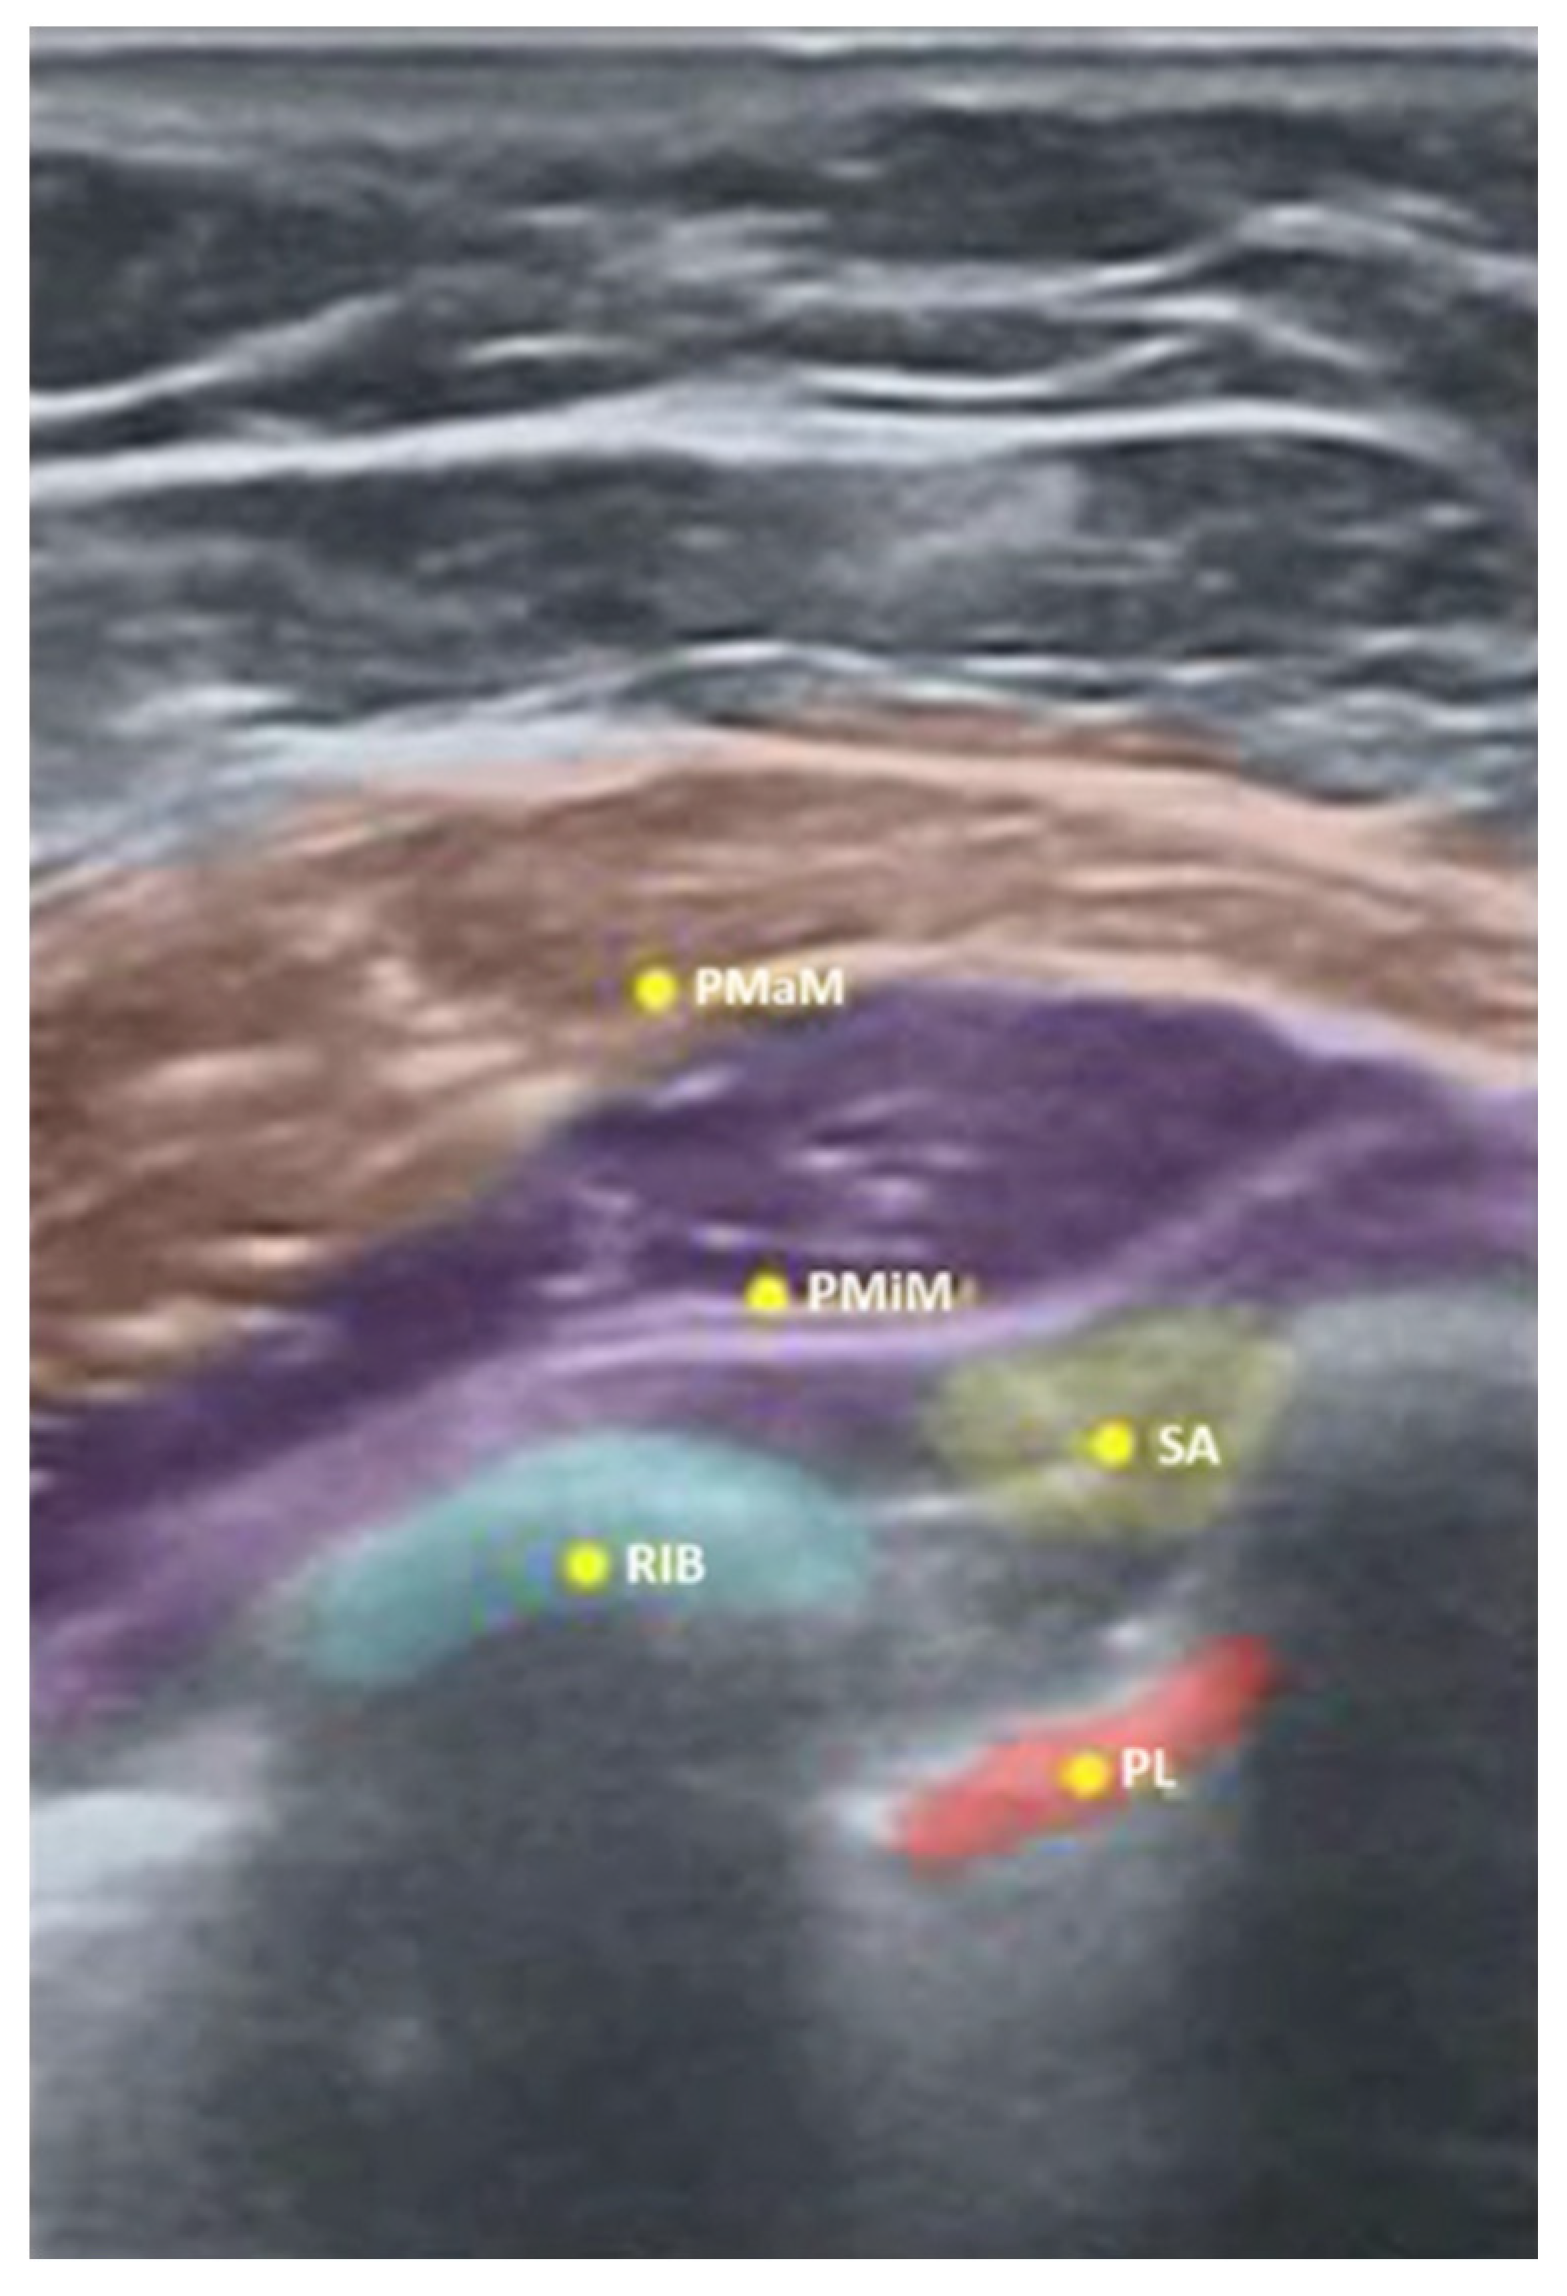

| Supraclavicular | First rib (FR) | 5 ± 0.01 | 4.98 ± 0.12 | 0.96 |

| Pleura (PL) | 5 ± 0.01 | 4.98 ± 0.12 | 0.96 | |

| Subclavian artery (SA) | 5 ± 0.01 | 4.98 ± 0.05 | 0.97 | |

| Brachial plexus (BP) | 4.9 ± 0.01 | 4.98 ± 0.04 | 0.99 | |